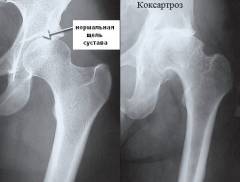

Рентген тазобедренного сустава — простой и информативный метод, позволяющий подтвердить диагноз и определить степень выраженности патологического процесса. Метод основан на «просвечивании» области сустава рентгеновскими лучами, которые поглощаются тканями организма с различной интенсивностью. Это исследование позволяет визуально оценить выраженность и характер повреждений внутрисуставных компонентов, а также выявить причины развития артроза.

Рентгенография тазобедренного сустава при коксартрозе может показать:

- сужение суставной щели;

- остеофиты на головке бедренной кости;

- остеофиты в области вертлужной впадины;

- деформацию суставных поверхностей костей;

- подвывихи и вывихи головки бедра.

При подозрении на коксартроз обязательно рентгенологическое исследование обоих суставов, даже если симптомы проявляются только в одном из них.